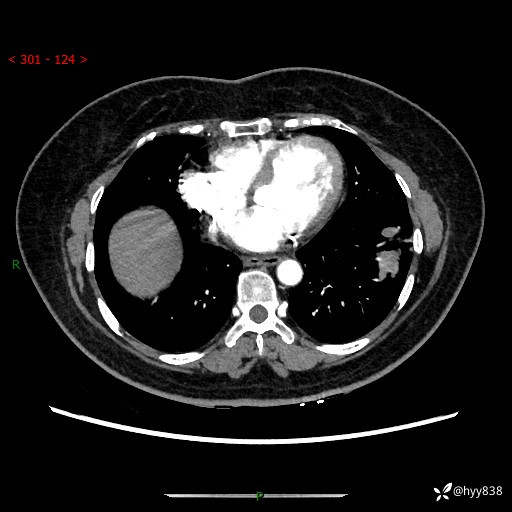

【现病史及既往史】:患者自诉2月前体检发现肺结节(左肺下叶约17mm,右肺上叶4mm),未予特殊处理,2024-10-12当地市第五医院门诊复查胸部CT提示右下肺结节(大小约3.3cm*3.9cm),患者无咳嗽、咳痰,无畏寒、发热、盗汗,无咯血,无胸闷、胸痛、呼吸困难,无恶心、呕吐,无腹痛、腹胀、腹泻等不适,现为求进一步诊治,门诊以“孤立性肺结节”收住我科。 患者本次起病来精神、食欲、睡眠尚可,大小便正常,体力、体重无明显变化。

【检查】:胸部CT增强检查